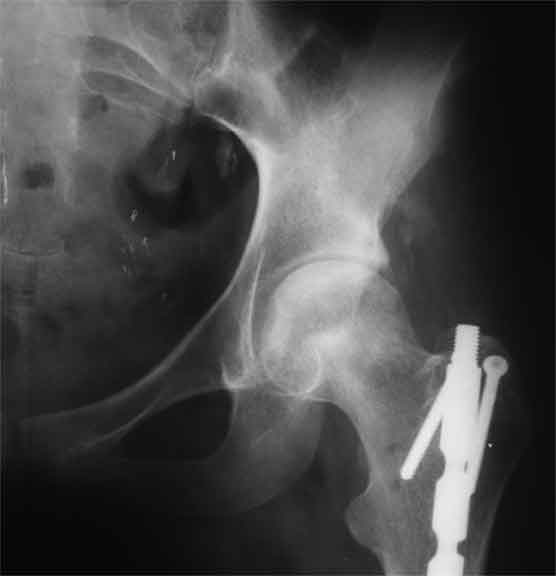

Насчет 8 см согласен с А.Н. Челноковым, это наверное ортопедическое за счет приводящей, сгибательной контрактуры и, возможно, колена. на ликвидацию укорочения у нас обычно уходит около 2-х нед. снимки в приложении, возможно не очень показательные, но других с ходу не нашел, завтра еще поищу.